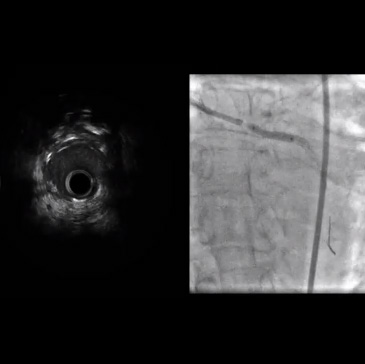

• La ecografía intravascular mostró un vaso muy estrecho con placa fibrocálcica considerable. A causa de estos hallazgos, se tomó la decisión de proceder con el Rotablator.

• La cuerda guía original se cambió utilizando un balón OTW por una cuerda guía RotaWire ™

• Se avanzó una oliva de 1,5 mm y se realizó una aterectomía rotacional.

• Una angiografía posterior mostró flujo TIMI-3 sin disecciones, pero aún con una estenosis residual significativa.

• Se colocó un stent liberador de fármaco (DES) de 3,5 x 16 mm con excelente expansión mediante fluoroscopía.

• Una ecografía intravascular mostró una subexpansión en la parte proximal del stent.

• Posteriormente se realizó una dilatación a alta presión con un balón NC Quantum Apex de 3,75 x 12 mm.

• La angiografía final demostró flujo TIMI-3, sin disecciones y sin estenosis residual en el sistema circunflejo izquierdo.